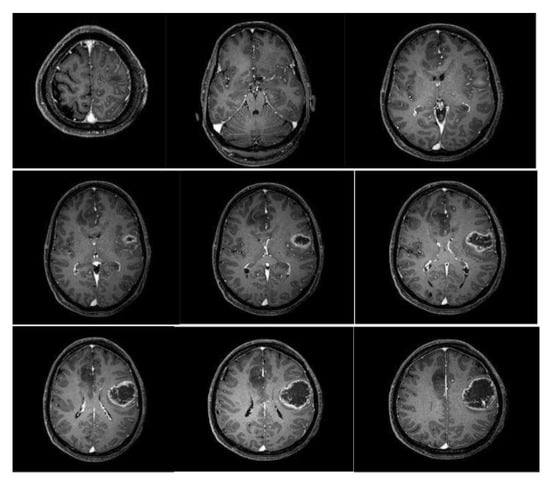

Mathematical Modeling and Analysis of Tumor Growth Models Integrating Treatment Therapy

by Mohsin Kamran, Johari Yap Abdullah, Afaf Syahira Ahmad Satmi, Maya Genisa, Abdul Majeed and Tayyaba Nadeem

Math. Comput. Appl. 2025, 30(6), 119; https://doi.org/10.3390/mca30060119 - 30 Oct 2025

This study presents a comparative analysis of tumor growth models based on logistic, exponential, and Gompertz formulations. Their response to therapeutic intervention is examined to identify which model shows better behavior with minimal decline of immune cells. The framework incorporates three main cell [...] Read more.

This study presents a comparative analysis of tumor growth models based on logistic, exponential, and Gompertz formulations. Their response to therapeutic intervention is examined to identify which model shows better behavior with minimal decline of immune cells. The framework incorporates three main cell populations as follows: natural killer cells, cytotoxic T cells, and tumor cells, along with treatment effects. Dynamical properties such as positive invariance, existence, boundedness, and equilibrium stability are investigated. Numerical simulations indicate that the logistic model gives more favorable treatment outcomes compared to the exponential and Gompertz models. The results also show a faster decline of immune cell populations in the exponential and Gompertz models than in the logistic model under varying drug flux. Full article